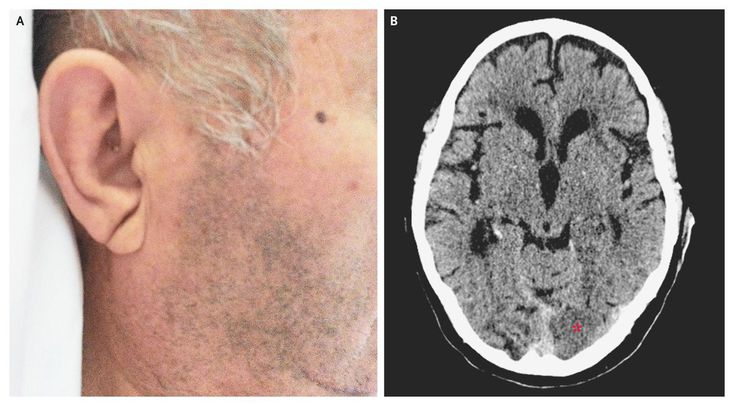

An 84-year-old man with hypertension, diabetes, and hypercholesterolemia presented to the emergency department with a 6-hour history of visual difficulty. Physical examination revealed a right homonymous hemianopia and no other relevant neurologic findings. A diagonal crease in each earlobe (Frank's sign) was noted (Panel A). Urgent computed tomography revealed a subacute occipital infarction in the territory of the left posterior cerebral artery (Panel B, asterisk), as well as many other old ischemic lesions. Frank's sign was originally described as a marker of coronary artery disease, with a moderate sensitivity (approximately 48%) and specificity (approximately 88%). This sign has been subsequently associated with other cardiovascular risk factors. The patient was treated conservatively, his course was uneventful, and he was discharged home 1 week after presentation, with persistence of the visual deficit.